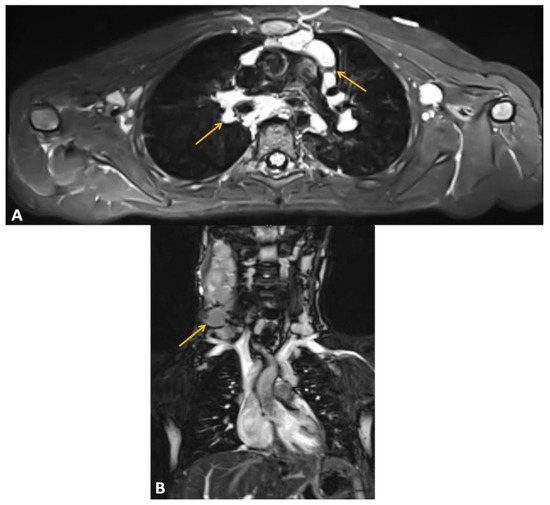

- Jończyk-Potoczna, K.; Potoczny, J.; Szczawińska-Popłonyk, A. Imaging in Children with Ataxia-Telangiectasia—The Radiologist’s Approach. Front. Pediatr. 2022, 10, 988645. [Google Scholar] [CrossRef] [PubMed]